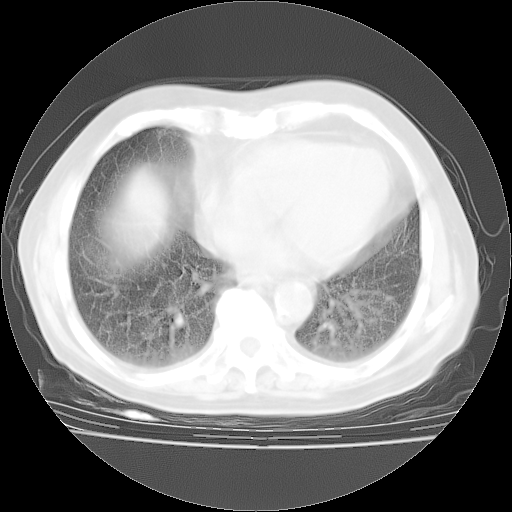

4月28日肺部CT——再次出现类似去年5月9日——磨玻璃样、间有“粟粒样”改变。

个人阅读4.14日肺部CT平扫:纵隔窗无异常,但肺窗示:双下肺内、后基底段有片絮状侵润影,部位以后基底段为著,以间质改变为主,呈急性肺泡炎征像,和首次住院影像学有相似之处。仅是个人读片,明日请相关专家再读片哈。其它建议同上。

1、108#的是4月14日的胸部CT(发此贴时还没看着28日的CT)。14日的胸部CT其实已经出现改变(如108#所述),个人认为28日的胸部CT除纵膈窗疑似有双侧胸膜增厚或少量胸积液(可行胸部B超明确)外,与4月14日对照病变有所加重;2、已经给予“异烟肼、利福平、乙胺丁醇”抗痨治疗?如果是,甲强龙80mg可缓慢减量;如果环磷酰胺已停用,暂不使用;3、中性粒细胞92%,明显升高,目前体温情况?注意合并细菌感染可能,使用左氧氟沙星情况下,是否联用B-内酰胺类抗菌药物?另外是查免疫全套非风湿全套。

今请临免主任会诊后认为:4月14日胸部CT已有双下肺间质性改变。患者病情复发多系激素减量过快不正规所致。目前甲强龙80mg/日,一周后酌情开始减量,不易过快。环磷酰胺若已停用,暂不使用。他同意目前抗菌药物使用,但应考虑是否加用B-内酰胺类抗菌药物(中性细胞明显增高);2、结核复发目前依据不足;3、若免疫全套各项指标正常,考虑多系特发性肺间质炎可能大。4、加强支持,并注意保护胃黏膜。

今上午去请教了临免、呼吸主任:1、介绍病史和阅读系列胸部CT一致认为:患者肺结核不考虑,仍为肺间质纤维化,目前处于急性肺泡炎阶段。2、若仍发热,可将甲强龙增至:80mg Bid静滴,同时鉴于中性增高,合并细菌感染可能,继续左氧氟沙星治疗,再联用B-内酰胺抗菌药物,如头孢哌酮--舒巴坦;3、停用抗痨药;4、目前甲强龙每日剂量160mg ,体温正常后再酌情减量;目前暂不用免疫抑制剂;4、不建议使用免疫增强剂等;5、加强支持治疗,鼓励患者进食;5、注意随访肝、肾功及血常规情况;6、因患者目前激素用量较大,加用胃黏膜保护剂,防止消化道出血可能。